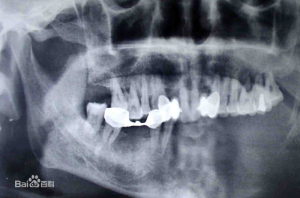

慢性骨髓炎X線片常示有死骨形成,病變多位於下頜體和下頜支,很少同時累及。而溶骨症X線片示無死骨形成,病變部位多同時累及下頜體和下頜支。